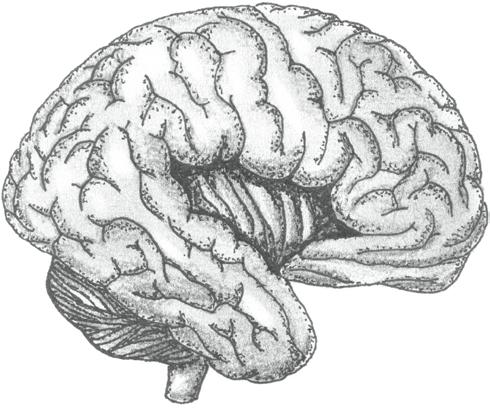

KONCOVÝ MOZEK (telencephalon) představuje nejobjemnější část lidského mozku. Je tvořen dvěma mozkovými polokoulemi (hemisperia cerebralia), které spolu velmi úzce spolupracují.

• Pravá mozková polokoule (hemisphera cerebri dextra) zpracovává především podněty s emočním doprovodem (včetně umění), chápe prostorové vazby, vládne představivostí.

• Levá mozková polokoule (hemisphera cerebri sinistra) reprezentuje zejména logické, matematické, analytické a technické myšlení a vládne také řečí.

Propojení obou polokoulí obstarávají mohutné svazky nervových vláken – mozkové komisury (commissurae cerebri). Největší komisurou je vazník neboli kalózní či bílé těleso (corpus callosum).

Vlastní hmota koncového mozku je členěna na šedou a bílou:

• Šedá hmota koncového mozku tvoří mozkovou kůru (cortex cerebri) na povrchu a podkorové struktury uvnitř hemisfér (sem patří např. bazální jádra a podkorové části limbického systému – jmenovitě amygdala a hipokampus).

• Bílá hmota koncového mozku leží v hloubce. Je tvořena gigantickým množstvím nervových vláken.

Povrch mozkových polokoulí je členěn řadou rýh a brázd do jednotlivých mozkových závitů – gyrů (gyri cerebri, jednotné číslo gyrus cerebralis). Popisujeme celkem pět mozkových laloků (lobi cerebri, jednotné číslo lobus cerebralis). Mozková kůra jednotlivých laloků obsahuje specifické korové oblasti (s jasně vymezenou funkcí) a dále asociační korové oblasti (které hrají roli propojovací, integrující a koordinující).

• Lalok čelní neboli frontální (lobus frontalis) je ve shodě se svým označením uložen v přední části mozku. Najdeme v něm mimo jiné oblast řízení motoriky (volní hybnosti včetně řízení produkce řeči a jemných pohybů očí) a korové oblasti čichu. Asociační oblast frontálního laloku (prefrontální kůra) zaujímá velký objem přední části frontálního laloku. Rozhodujícím způsobem ovlivňuje prožívání i chování, paměť a myšlení, motivaci i osobnostní charakteristiky

(včetně motivů, zájmů či kultivace chování a společensky adekvátních forem projevu s tlumením nevhodných a agresivních prvků). Vazba prefrontální kůry na psychické aspekty prožívání, chování a osobnosti člověka je nesporná.

• Lalok spánkový neboli temporální (lobus temporalis) ve svých neuronech zpracovává informace ze sluchového a rovnovážného čidla. Umožňuje porozumění řeči. Asociační oblasti se podílejí na mnoha funkcích včetně učení, paměti či chování.

• Lalok temenní neboli parietální (lobus parietalis) obsahuje především korové oblasti kožní citlivosti (senzitivity), chuti a dále asociační oblasti.

• Lalok týlní neboli okcipitální (lobus occipitalis) nese kromě asociačních oblastí zejména korové oblasti zrakové.

• Lalok ostrovní neboli inzulární (lobus insularis) je překryt lalokem spánkovým a jako jediný z mozkových laloků není na povrchu mozku vůbec patrný. Jeho funkce souvisí obzvláště s emočním prožíváním a řízením vnitřních orgánů a funkcí organismu.